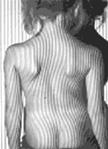

Визуальная диагностика сколиоза основывается на

отклонении линии остистых отростков от среднего положения и смещении

анатомических структур относительно срединной линии туловища. В качестве

клинических признаков развития сколиоза, доступных при осмотре следует отметить

(рис. 2.1):

Рис. 2.1 Клинические (внешние) признаки сколиоза

- асимметрию надплечий;

- отклонение линии остистых отростков от средней

линии;

- асимметрию высоты стояния лопаток;

- асимметрию расстояний между углом лопаток и

линией остистых отростков;

- асимметрию «поясничных» треугольников (талии);

- мышечный «валик»;

- асимметрию расположения крыльев подвздошных

костей.